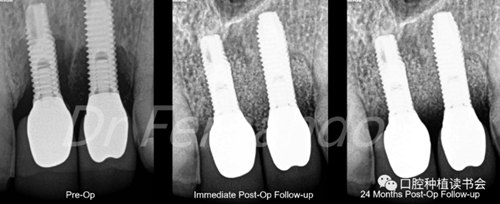

盡管手術(shù)治療似乎能改善結(jié)果;但只有將手術(shù)治療和骨再生相結(jié)合才能獲得更高的成功率。Schwarz等人發(fā)現(xiàn)這種再生手術(shù)治療有2年以上的滿意效果,能使種植體周圍的骨吸收停止,探診出血率由80%降至34%(圖5 )。

圖5通過手術(shù)治療,種植體周圍獲得骨再生,術(shù)后2年效果穩(wěn)定(圖2、圖4相同病例)